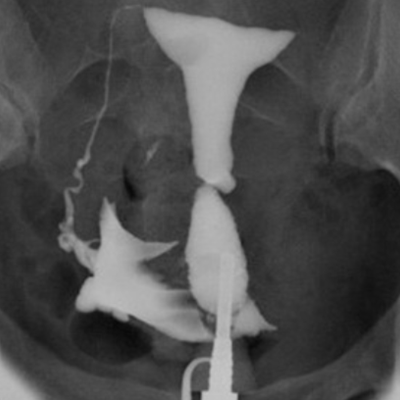

子宮卵管造影(hysterosalpingography:HSG)は、造影剤を子宮腔内に注入し、子宮内腔、卵管の陰影から子宮腔の状態、卵管の疎通性および骨盤腔内の癒着を判定する検査です。

リピオドール®の臨床成績(子宮卵管撮影)

対象:子宮卵管造影を実施した1,050例(うち原発不妊又は続発不妊患者は852例)

方法:月経終了後4、5日に造影剤としてリピオドール®480注10mLを使用し、子宮卵管造影を実施した。

結果

総症例1,050例において本剤の造影能に良好な成績が得られました。